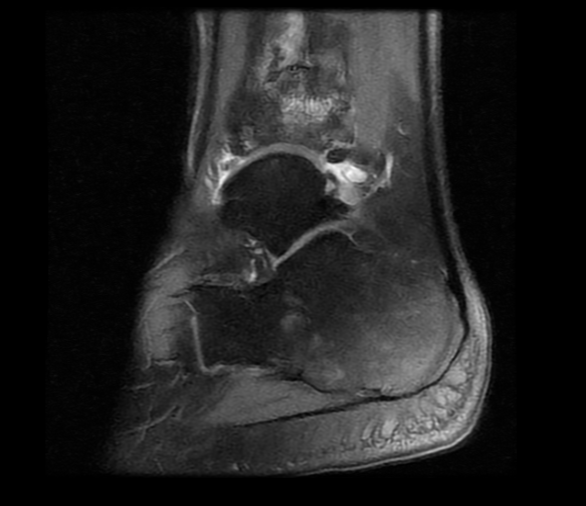

Arthritic flatfoot

Pre-op MRI